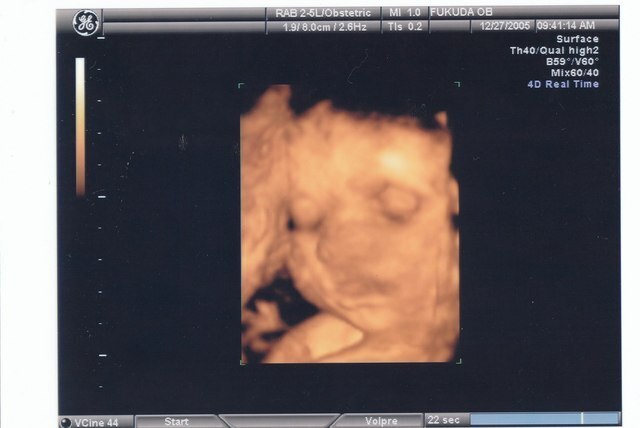

3Dと4Dのエコー写真、違いは?

3Dのエコー写真は2Dよりも複雑な角度で超音波を当てているので、赤ちゃんが立体的に見え、2Dのように説明が必要なことはあまりありません。

4Dのエコー写真は3Dエコー写真が動画になったもので、より、実物に近い赤ちゃんの姿が見られ最近人気です。妊婦健診とは別に、4Dエコーの設備がある病院へ撮影のために訪れる方も増えています。